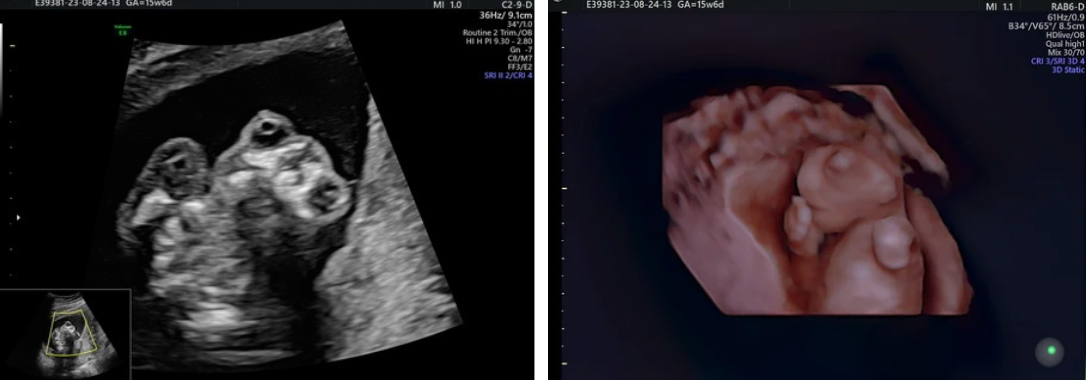

“Povestea doamnei M.O. este cea a unei tinere de 28 de ani din Bistrița, aflată la prima sarcină. Particularitatea în cazul ei a fost faptul că erau gemeni în doi săculeți diferiți și cu două placente, dar unul din feți avea o malformație incompatibilă cu viața, numită anencefalie. Termenul medical corect este de secvență acranie-exencefalie-anencefalie și constă în lipsa de formare a cutiei craniene, ceea ce expune creierul fetal la acțiunea distrugătoare a lichidului amniotic. Cu trecerea săptămânilor creierul este practic distrus în întregime. Această patologie apare destul de rar, o dată la aproximativ 1000 de sarcini și, conform studiilor publicate în 2019, poate fi diagnosticată în proportie de 100% la ecografia de 12 săptămâni. În cazul sarcinilor cu un singur făt, recomandarea medicală este relativ simplă și anume de a întrerupe cursul sarcinii datorită letalitații uniforme. Dar în cazul sarcinilor gemelare lucrurile se complică, mai ales când celălalt geamăn este sănătos, iar aceste cazuri sunt de obicei îndrumate către centre cu expertiză în diagnosticul și managementul afecțiunilor fetale fiind apanajul Medicinei Materno-Fetale. Mă bucur și apreciez faptul că doamna M.O. și-a pus încrederea în mâinile mele, alegând Departamentul de Medicină Materno-Fetală al spitalului nostru înaintea centrelor anterior menționate.

Prima evaluare a fost la 15/16 săptămâni, când am putut confirma diagnosticul de anencefalie la unul din feți și am putut evalua celălalt geamăn pentru anomalii structurale.

În cazul sarcinilor gemelare bicoriale (cu două placente) procedura constă practic în injectarea intracardiacă a unei substanțe care oprește inima fătului malformat. Acest lucru se face printr-o puncție transabdominală (ca la amniocenteză) sub ghidaj ecografic și cu anestezie, iar în Departementul nostru această procedură are loc în sala de operație. Ulterior fetucidului selectiv, geamănul malformat suferă treptat un proces de “mumificare”, uneori până la resorbție aproape completă.